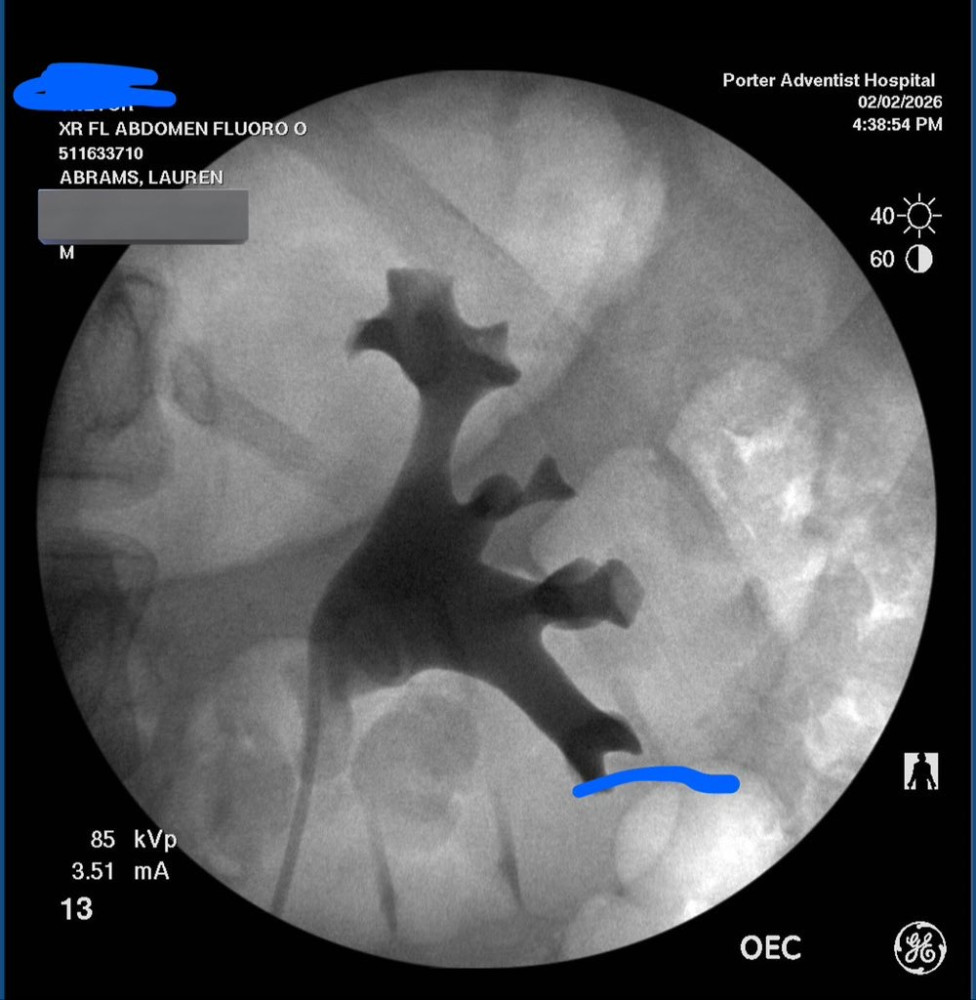

This is imagery taken during my last operation showing the kidney and the ureter.

I have been in and out of the hospital a total of 5 times and have had 3 emergency surgeries since January 9th. My left kidney an ureter are extremely damaged from a stent that was placed during one of the operations. I still have 4 more weeks of recovery ahead however we are switching me to home healthcare. This is very costly and I’ve ran out of funds since I’ve been out of work for a month. All the money collected from this fundraiser will go towards medical costs and copays. I appreciate any and all help.